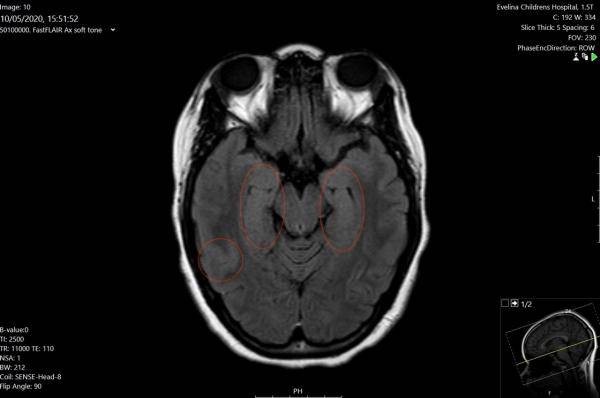

醫生認為這是妮雅的大腦發炎導致,病毒攻擊了妮雅的大腦,似乎也改變了她的性格。她被診斷出患有腦炎,會導致幻覺、癲癇,語言、聽力和記憶力產生問題等併發症。

兩周後,她的病況逐漸好轉,終於能自己呼吸,似乎已戰勝新冠病毒。但轉至普通病房幾天後,其病情卻再度惡化,而被送回加護病房;這次受影響的是她的大腦而非肺部,她開始經常產生幻覺、聲音和行為退化至像4、5歲的小朋友。